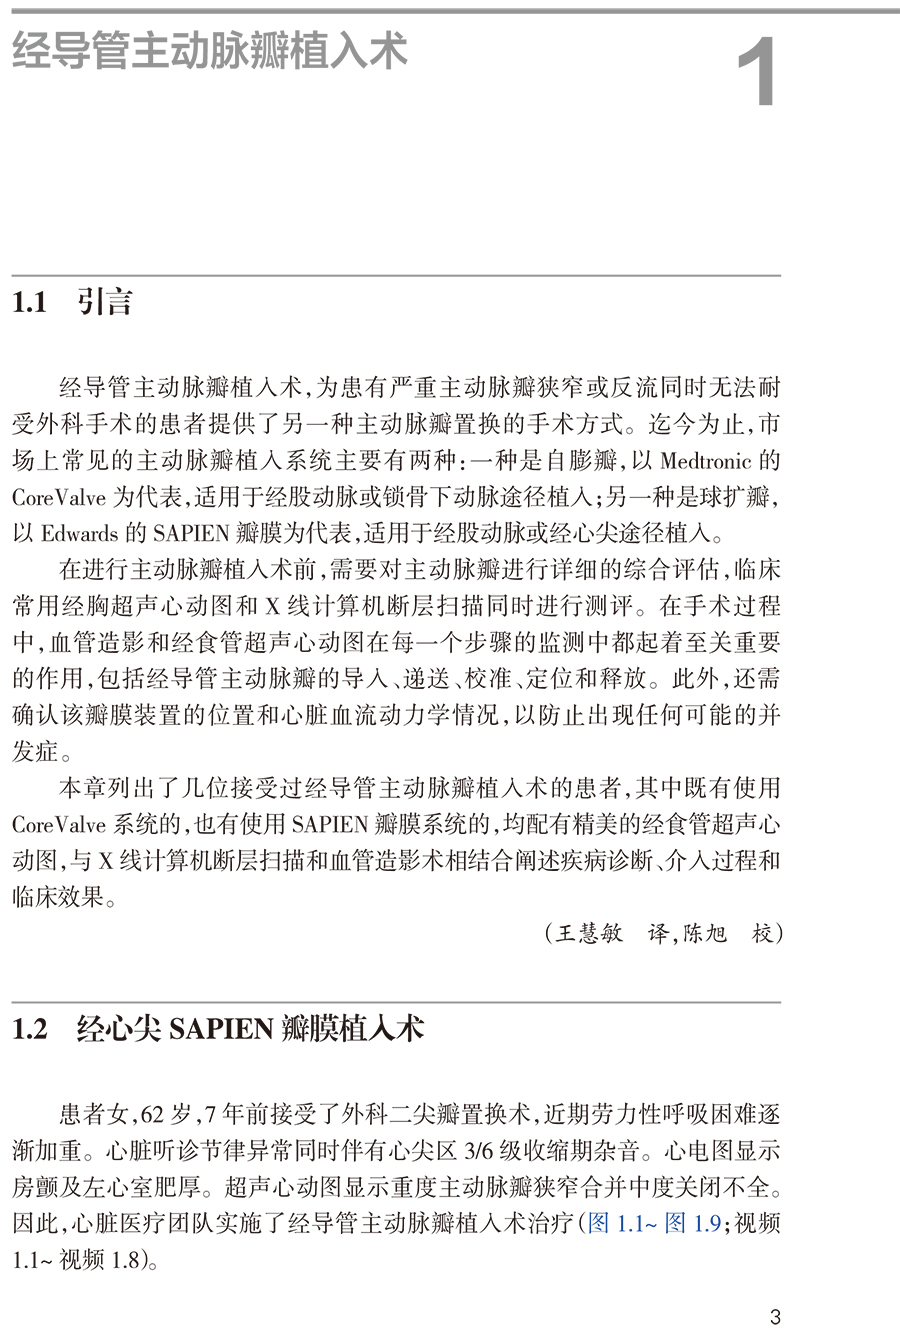

1.2 经心尖SAPIEN 瓣膜植入术 /3